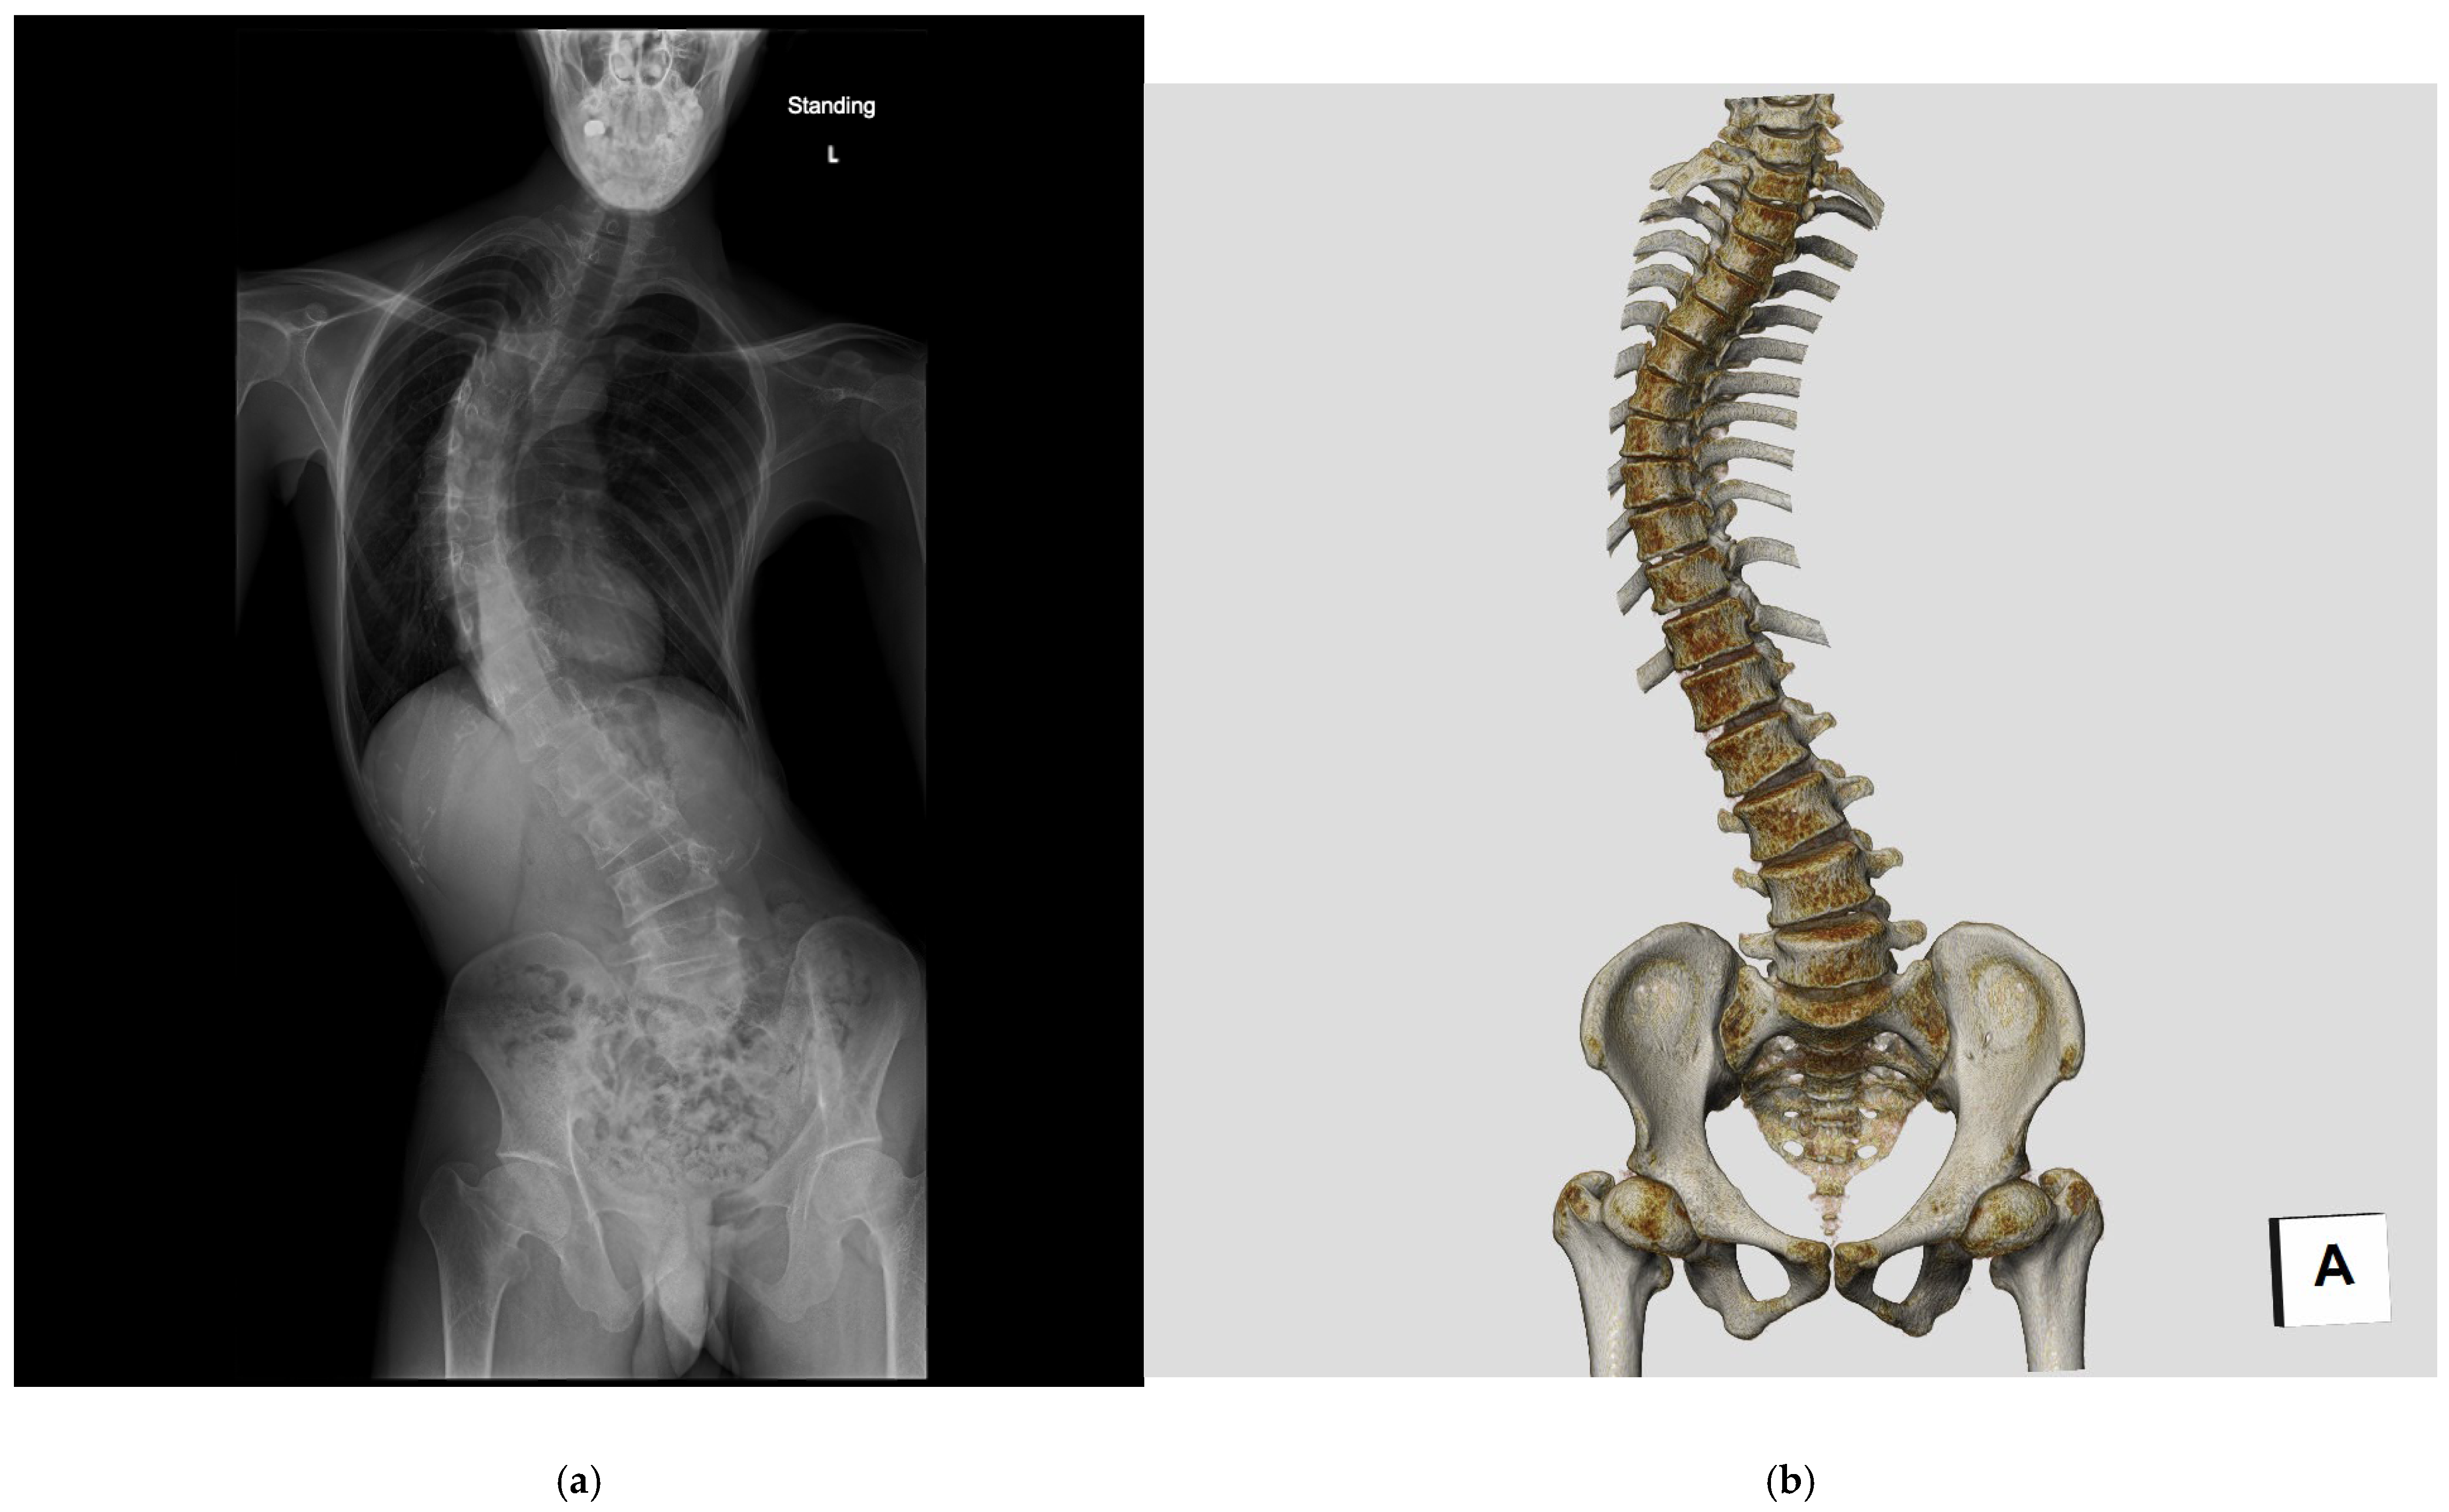

1. Introduction